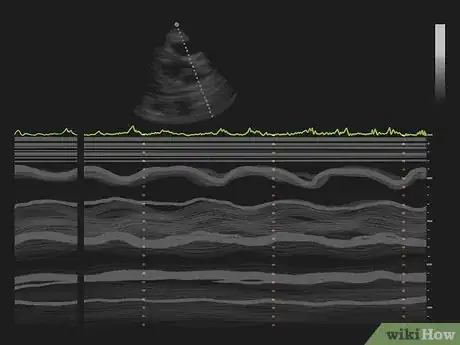

An echocardiogram enables the doctor to generate images of your heart in real-time using ultrasound. Ultrasound, or sounds higher than we can hear, are projected through your body and a machine reads the sound waves that are bounced back, and converts them to an image. It is not harmful to you. This is valuable for diagnosing several heart conditions, planning treatments, and the effectiveness of treatments. Many patients find it useful to understand the images and what the doctor is looking for.[1]

3Watch the monitor to determine what techniques the doctor uses. There are several different techniques the doctor may use. They enable the doctor to make different measurements.[9]

- M-Mode. This technique generates a outlines showing the heart's size, the chambers, and the thickness of the walls of the heart.